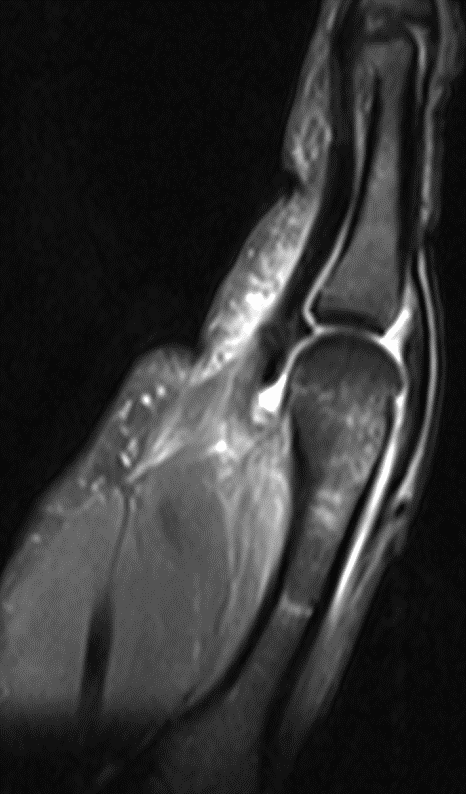

(Левый) Пациент, длительно страдающий латеральной нестабильностью голеностопного сустава и недавно перенесший вывих. При МРТ в аксиальной плоскости на ППВИ в режиме FS определяется сочетание признаков острой и хронической травмы. Выявляются разрывы ПТМС, глубокого и поверхностного слоев дельтовидной связки.

(Правый) У этого же пациента при МРТ в коронарной плоскости на Т2ВИ в режиме FS визуализируется отек дельтовидной связки в области ее прикрепления к таранной кости. Также наблюдается полный разрыв ПМС. Поверхностный слой дельтовидной связки отделен от области прикрепления к медиальной лодыжке. (Левый) Пожилой пациент, предъявлявший жалобы на ощущение «проваливания» в голеностопном суставе. При МРТ в коронарной плоскости на Т2ВИ в режиме FS определяются разрывы ПМС и большеберцово-пяточной порции поверхностного слоя дельтовидной связки, а также медиальный подвывих пяточной кости.